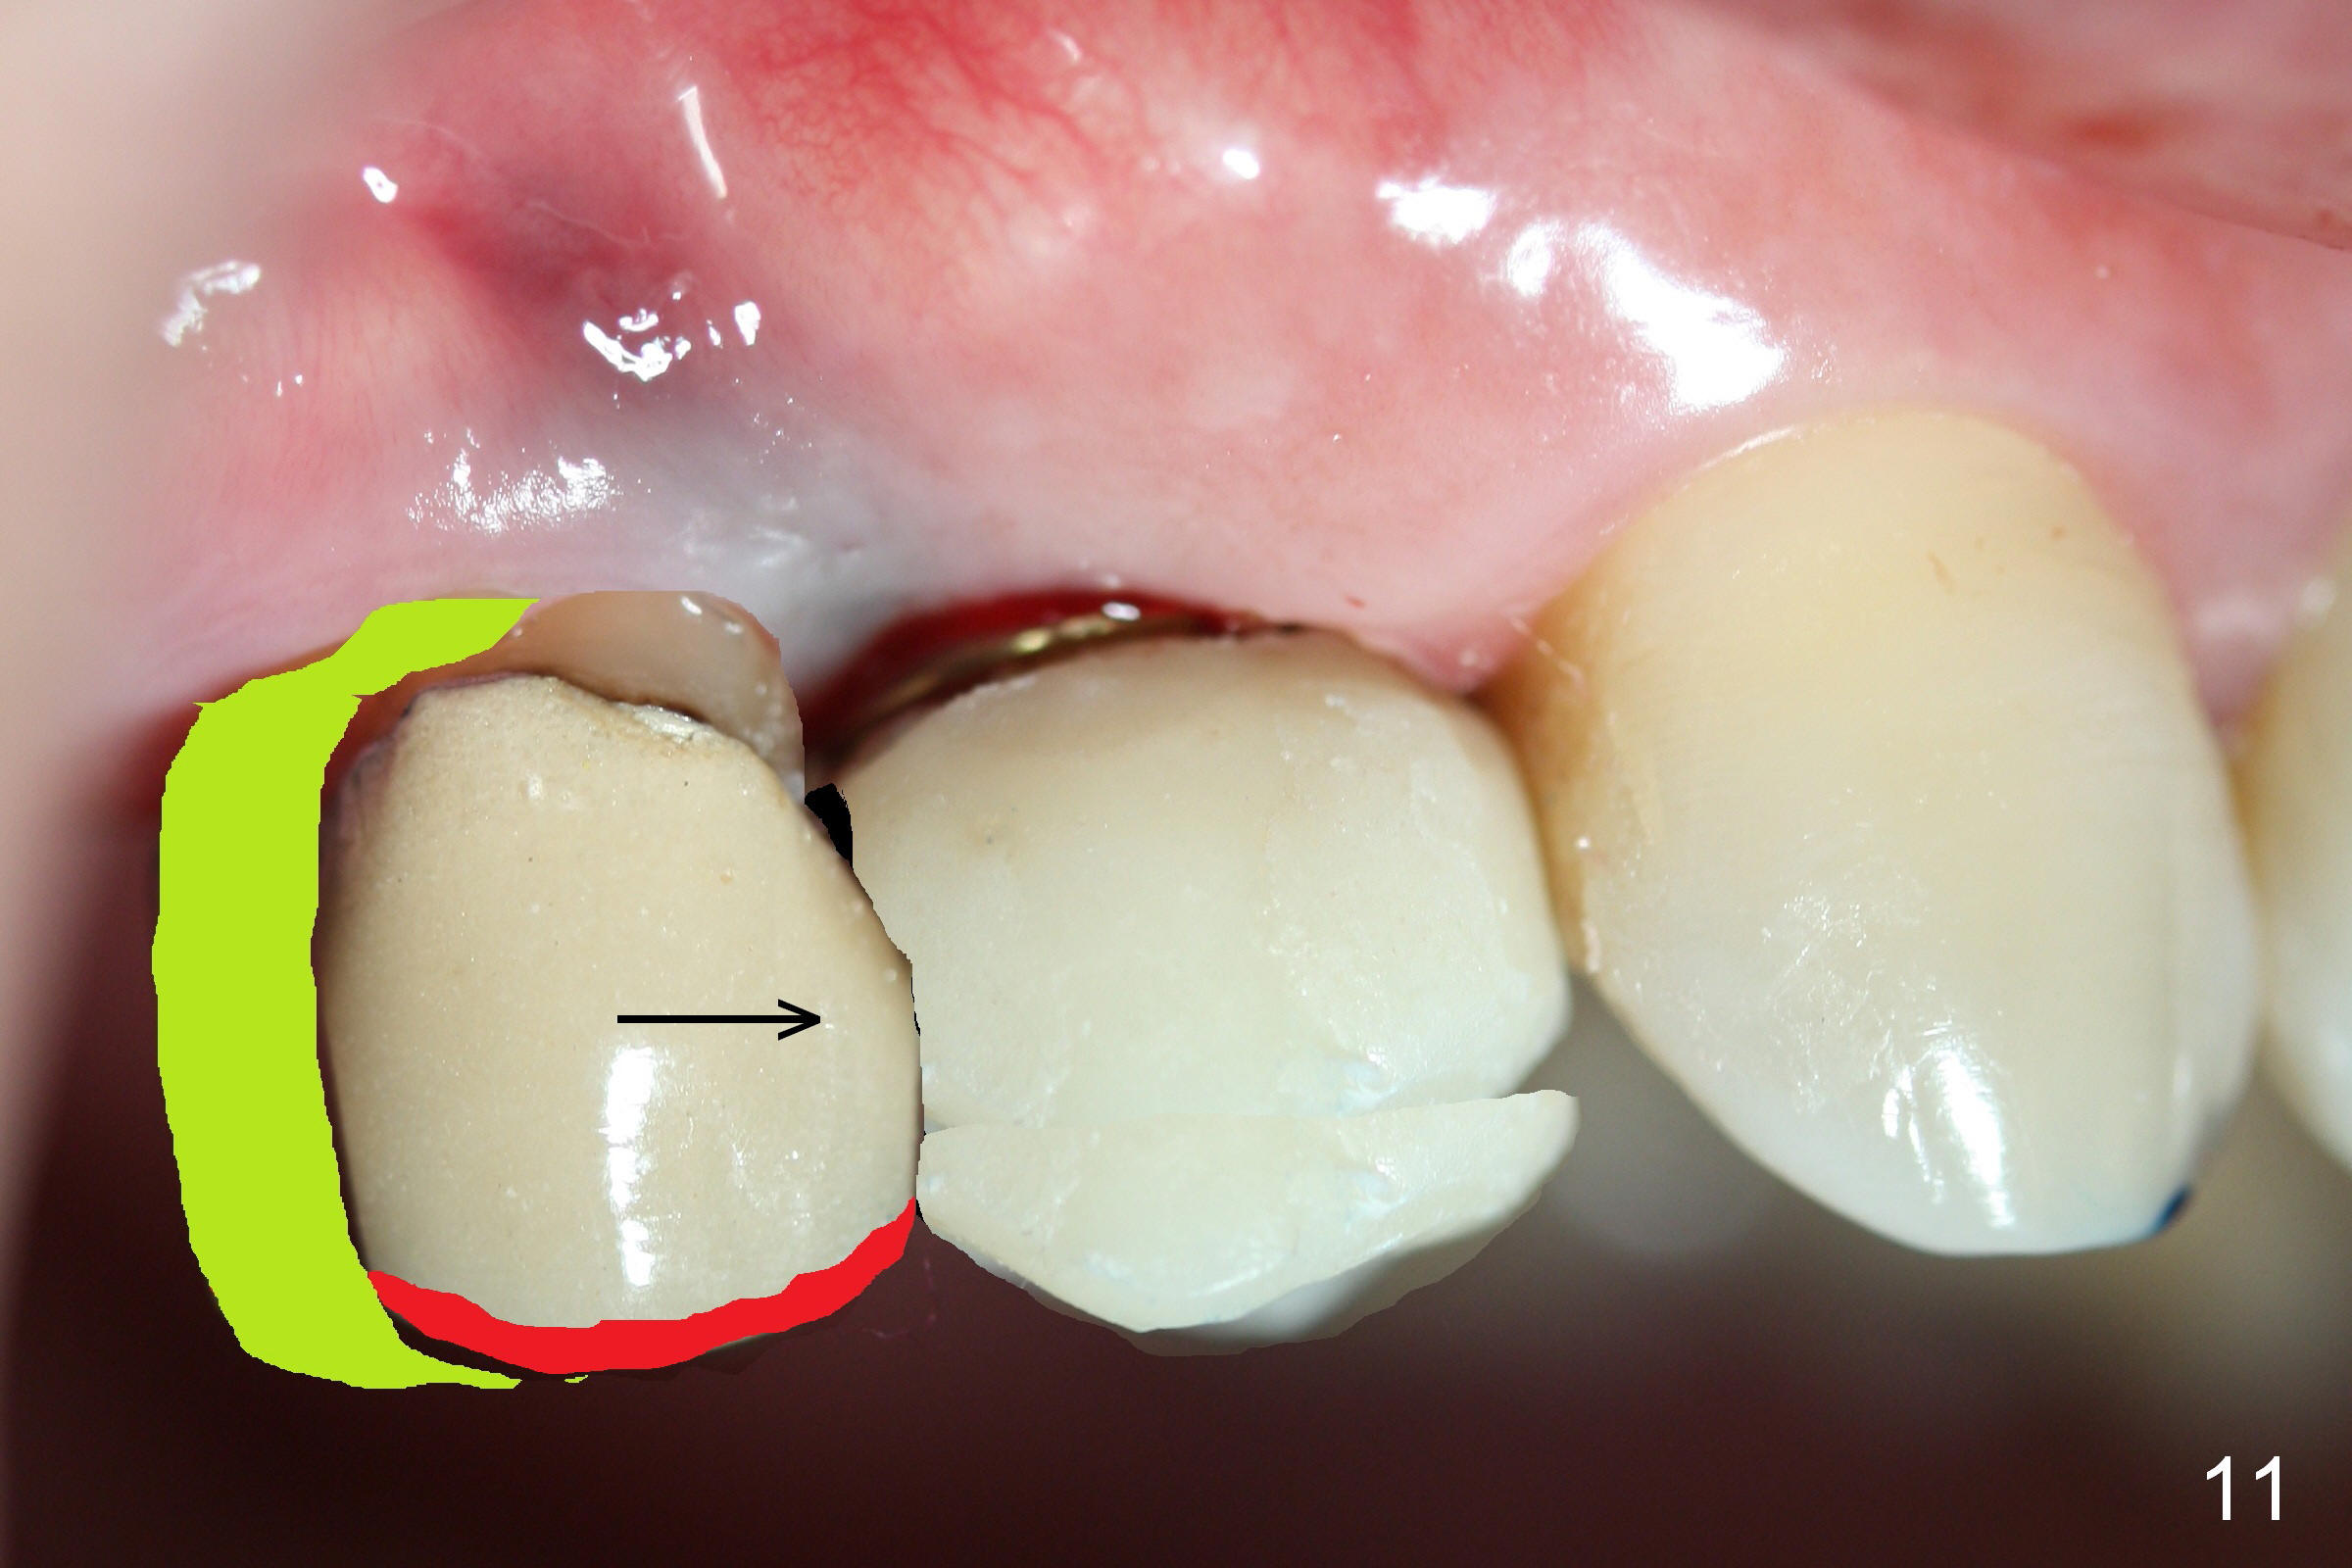

The distal surface of the provisional will be reduced (Fig.9,10 D), whereas the occlusal surface will be increased (Fig.9 O). If needed, the occlusal surface of the distalized tooth #4 will be reduced (Fig.9 red area) so that there is no interference for tooth to move. Hooks will be placed on the buccal and lingual surfaces of the provisional (Fig.10 green curved lines). Power chains will be placed on the hooks and wrapped around the tooth #4. In due time, the tooth will be mesialized (Fig.11 arrow). Implants at the sites of #2 and 3 will be placed in more appropriate positions.